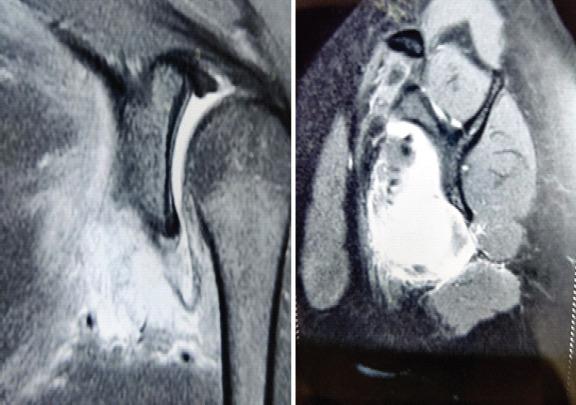

A 22-year-old female presented to us with a complaint of pain in the shoulder for 6 months. On clinical examination, external rotation and internal rotation were restricted. On evaluation, X-ray was normal, while magnetic resonance imaging and computed tomography scan showed 1.5 cm × 1 cm lesion in the subscapularis extending in the shoulder joint. First an ultrasound-guided biopsy was performed, which was followed by open excision biopsy revealing myositis ossificans. Post-operative period was uneventful with the patient achieving full range of motion after 15 days of surgery. Shoulder functional score Constant-Murley score (0-100) increased from 66 to 95, and University of California score (0-35) improved from 17 to 34 from pre-operative to post-operative period, respectively.

一名22岁女性因肩部疼痛6个月前来就诊。临床检查发现,外旋和内旋受限。经评估,X线检查正常,而磁共振成像和计算机断层扫描显示肩胛下肌有一个1.5厘米×1厘米的病变延伸至肩关节。首先进行了超声引导下活检,随后进行了开放性切除活检,结果显示为骨化性肌炎。术后恢复顺利,患者在术后15天达到了全关节活动范围。肩部功能评分Constant-Murley评分(0-100)从术前的66分提高到了95分,加利福尼亚大学评分(0-35)从术前的17分提高到了34分。